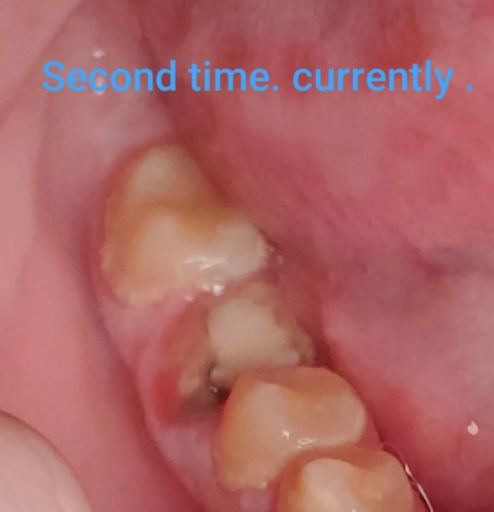

I have a good set of teeth minus my top front tooth. I broke it in half on asphalt, had a temp filling for 10 years and then got a crown. The crown left my tooth hurting so eventually ended up getting a root canal. Now almost a year later at my routine exam they did x-rays and found a fracture on the tooth. The crown is not fractured but the nub of a tooth underneath is....my dentist thinks it likely fractured during the root canal procedure. Currently I have no pain or issues, but I'm wondering what the long term worse case scenario would be or what I should be looking for as a sign of deeper ongoing damage or anything else I should be looking to do now to prevent worse damage later.

Hi . My crown fell off my root canal . I had the root canal done a little over a month ago . A week later the crown fell off . I went back and they put a new crown on . But now it fell off . The root canal tooth also seems to hurt in a way . Its red...